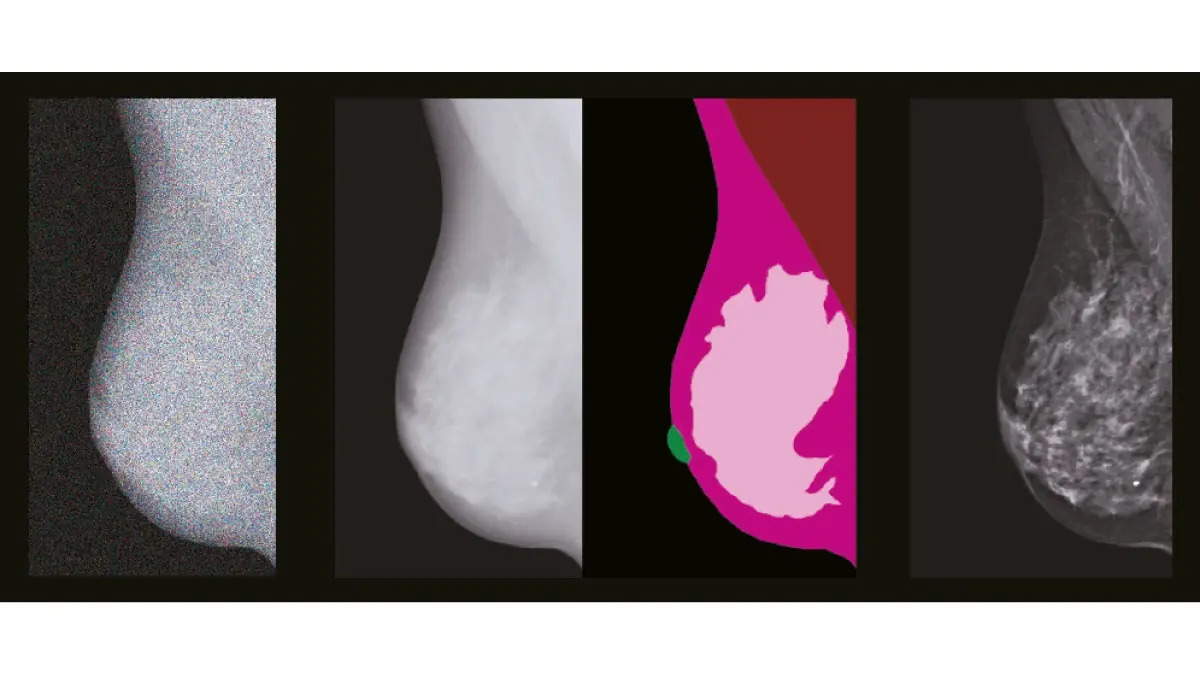

TRUVIEW®M2: Tecnología de procesamiento con IA para densidades mamarias variadas

Esta tecnología propietaria utiliza procesamiento de imagen con inteligencia artificial optimizado para diferentes tipos de tejido mamario. Permite detectar detalles muy finos incluso en mamas densas. Mejora en la definición de estructura, bordes y microcalcificaciones, adaptándose a la anatomía individual de cada paciente.